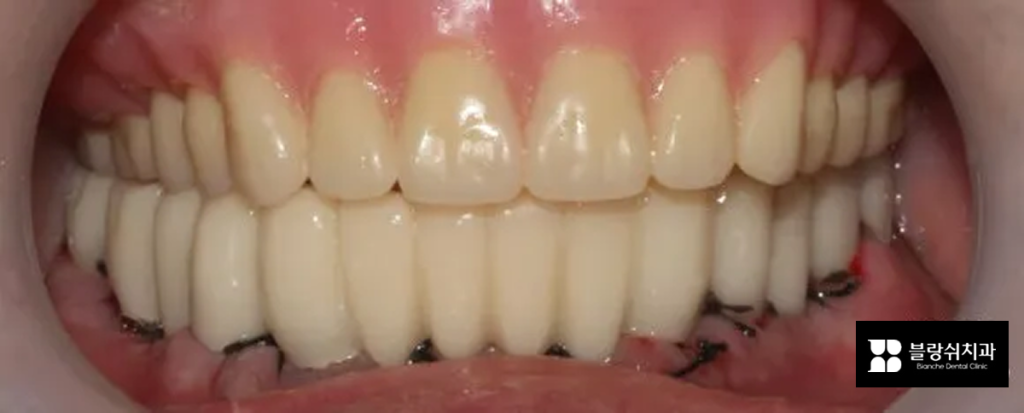

마지막 사진은 아무것도 없던 공간에 임플란트가 식립되고 그 위에 치아색 레진 임시치아가 장착된 모습입니다. 자연치와 완전히 똑같은 느낌은 아니지만, 임시틀니에 비해 고정감과 만족도가 훨씬 높고, 특히 뼈이식이 함께 진행된 경우에는 임플란트가 잘 자리 잡는 데도 도움이 되는 방식으로 알려져 있습니다.